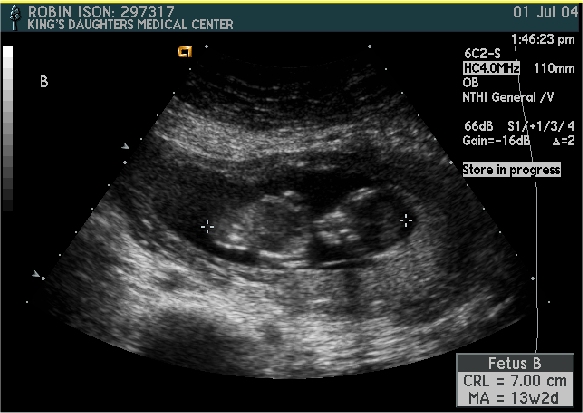

Baby B

Pictures from Ultrasound at 13 1/2 weeks.